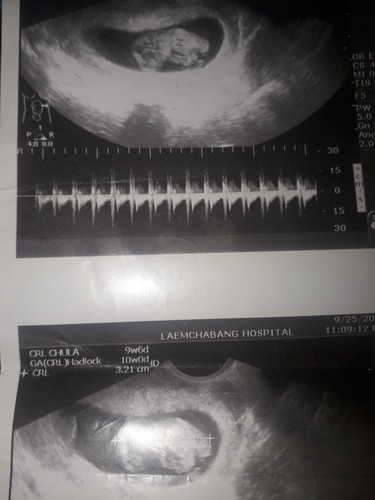

อันนี้ตอนซาวด์เจอเด็กค่ะน้องนอนขดตัวเหมือนนอนหลับค่ะแต่ไม่มีชีพจรเลยท้องจะเข้า6เดือนแล้วมีอวัยวะครบแล้วค่ะน้องเป็นผู้ชาย😭

ดูจากรูป น้องน่าจะไม่อยู่ตั้งแต่2เดือน แต่น้องไม่ได้ขับออกมาตามธรรมชาติ และคุณแม่ไม่ได้อัลตร้าซาวด์เลย เลยเพิ่งจะรู้ตอน5เดือน สู้ๆนะคะ เป็นกำลังใจให้นะคะ รักษาร่างกายแล้วค่อยมีอีกครั้ง ปล.เราก็เคยแท้งตอน2เดือนค่ะ